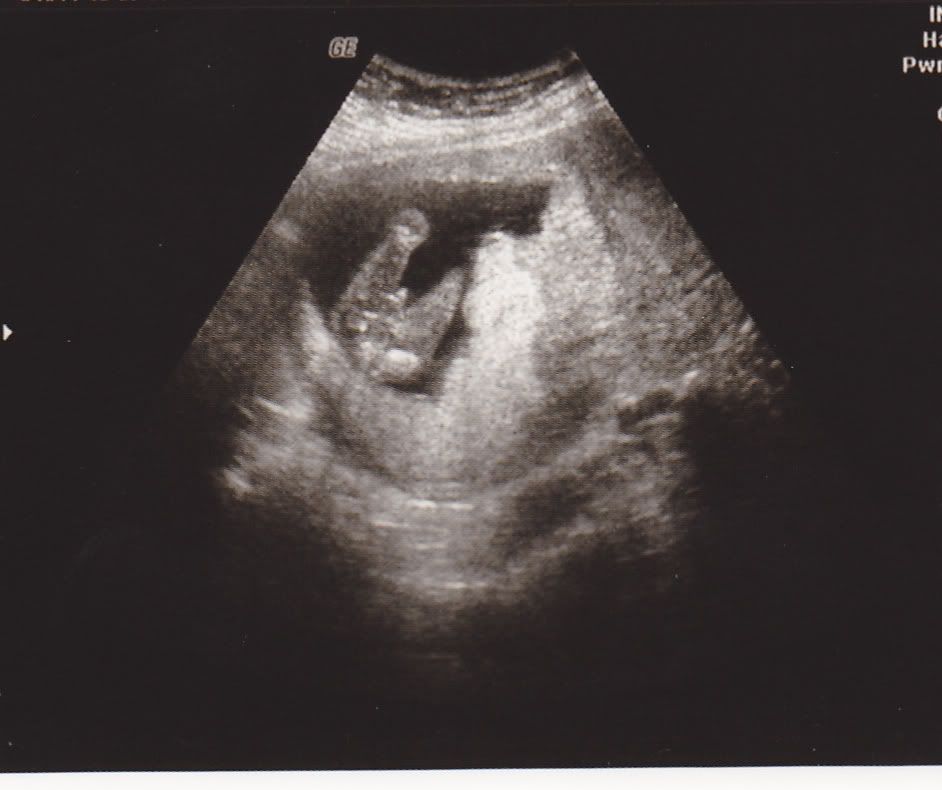

Baby Boy Potty Shot (16wks) concerned is cord HELP! Pic attached

Boy Potty Shot 16 Weeks . I’ve looked at 100’s of confirmed boy potty shots on the internet and not one looked similar. Very easy to tell if it's a boy. Does anyone have potty shot 16 weeks. Hi, i had a gender scan at 16 weeks and they confirmed girl but i’ve just seen a very similar potty shot to mine on a gender page. I could see boy bits at 13+4 scan. The bladder is more likely to be seen in a boys potty shot due to their low bladder position and their genitals being on top of their lower abdomen. I want to see other people boy potty shot to compare to my 16 week one since i have been told now it may be a girl. She point the arrow at something, but it looks like the umbilical cord in the way and not the part of a girl or boy. Will attach my 16 week scan so u can see how clear they are then. The bladder images as a black circle under the penis and scrotum and to an untrained eye may look like the anus. To me it looks too long and dead straight at the sides so is more similar to the cord. Bit of a back story, we had a scan at 16 weeks and was told girl, the sonographer took a long time to see the gender as baby was in awkward position and was… I went for a private gender scan yesterday and the sonographer took a while whilst locating the. Currently 16 weeks pregnant with baby no.2 as i already have an 18 month old ds.